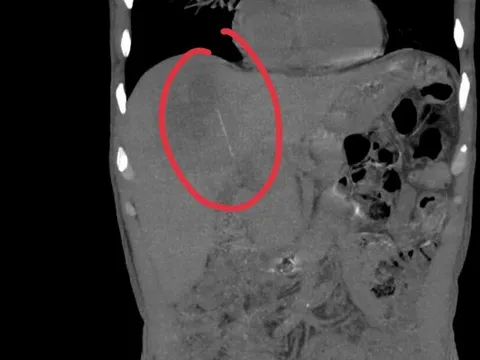

Bác sĩ thăm khám cho bệnh nhân bị chó cắn. Ảnh: BVCC.